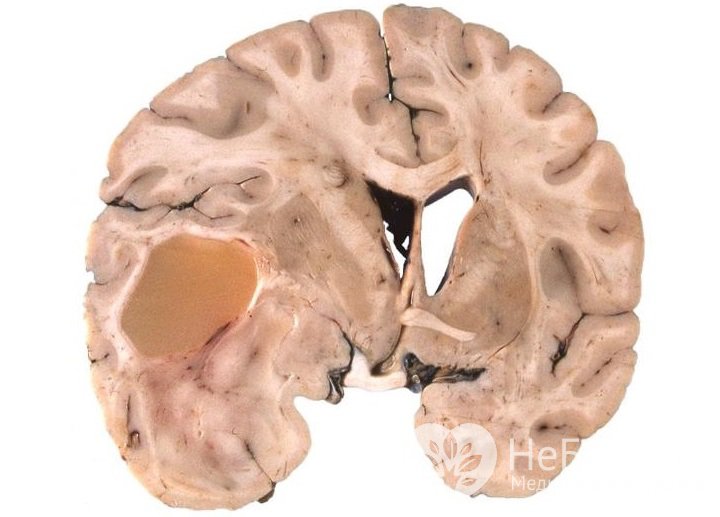

У взрослых астроцитомы обычно локализуются в белом веществе больших полушарий головного мозга. У детей они чаще поражают ствол мозга, мозжечок или зрительный нерв.

Точный диагноз с определением степени злокачественности опухоли можно поставить только по результатам гистологического анализа. Получить биологический материал для проведения этого исследования возможно при стереотаксической биопсии или в ходе оперативного вмешательства.